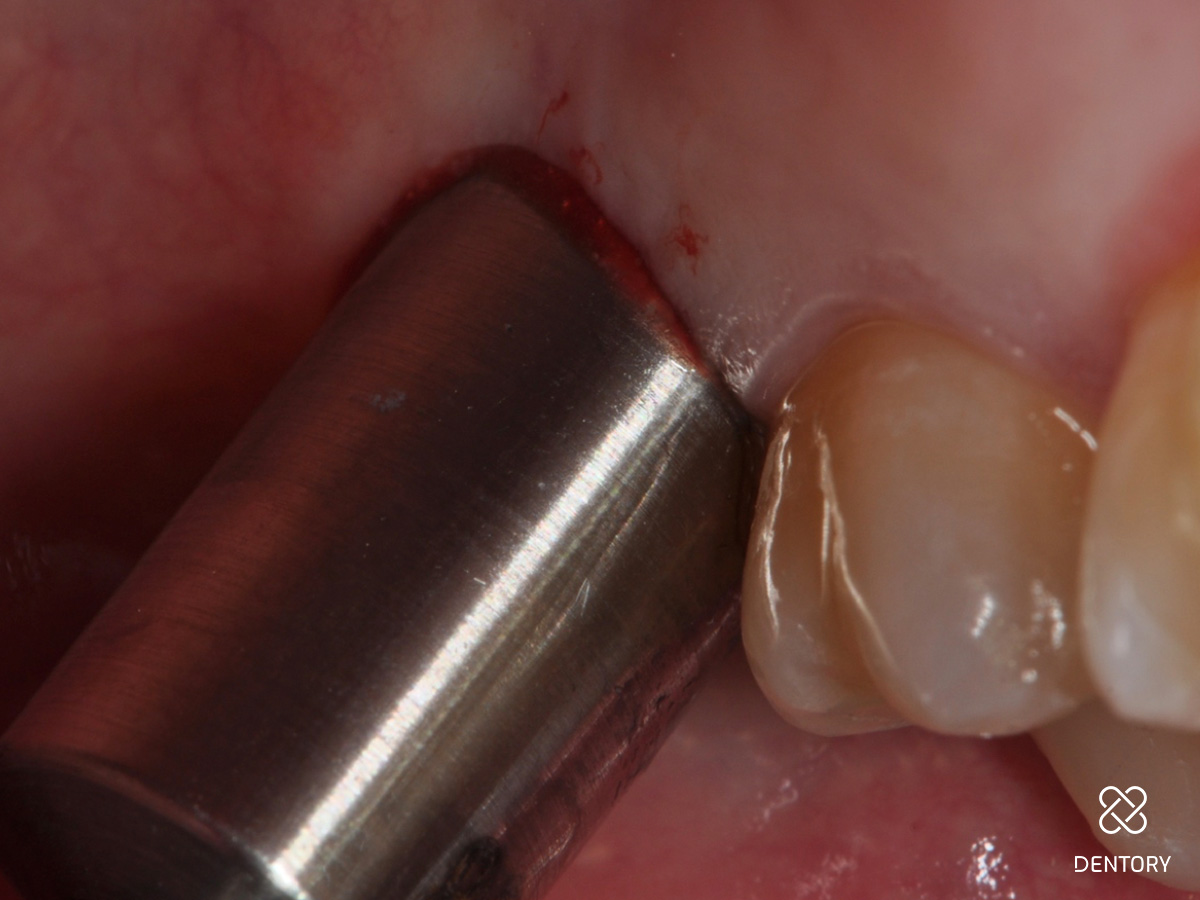

Abbildung 7

Okklusale Ansicht der Extraktionsalveole. Die Entfernung des Saumepithels erfolgt mit einem grobkörnigen Diamantbohrer.